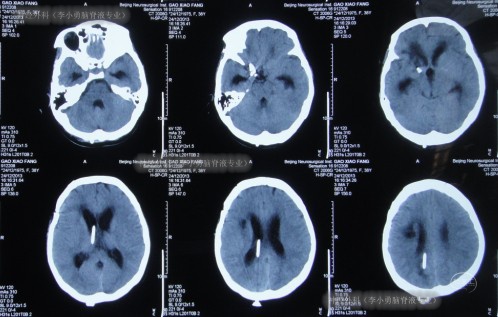

考虑分流管压力过高,将“分流管泵”压力从2.0调至1.5,并腰穿测压为110mmH2O。调压后患者神志逐渐转清,能轻声言语、写字,但反应仍迟钝,于2013年12月24日即分流术后22天,查头颅CT示脑室较前有所减小,脑室周围水肿明显减轻(图-9)。根据此次头颅CT以及症状改善的结果,建议转院康复治疗。

图-9:分流术后22天头颅CT

2014年1月2日即转入第3家医院后第1天(分流术后第31天)查头颅CT(图-10)示脑室扩张和脑室周围水有所加重。

图-10:分流术后31天头颅CT

次日即2013年1月17日,查头颅CT(图-11)示脑室有所再度扩张,腰穿测压140,脑脊液白细胞1100,医生考虑此种情况与相关药物减量有关,遂即恢复“高剂量”的使用,并加口服相关药物治疗。

图-11:分流术后46天头颅CT

2014年1月20日(即第3家医院治疗21天,又即脑积水分流术并发症进行了49天治疗后仍脑积水、颅内感染),转住入李小勇脑脊液专业,入院时:反应迟钝,张口困难、不能伸舌、不能经口进食,不能言语(图-12);虽可遵命活动肢体但动作微小;右额颞可见长约15cm弧形手术切口疤痕(动脉瘤夹闭手术疤痕);右枕部可见长约5cm纵手术切口疤痕(脑室腹腔分流术疤痕)。颈项强直。双侧瞳孔不等,对光反射迟钝。

图-12:入院时

入院当天进行头颅CT示脑积水分流术后脑室显著扩张,脑室周围水肿(图-13)。

图-13:2014年1月20日头颅CT